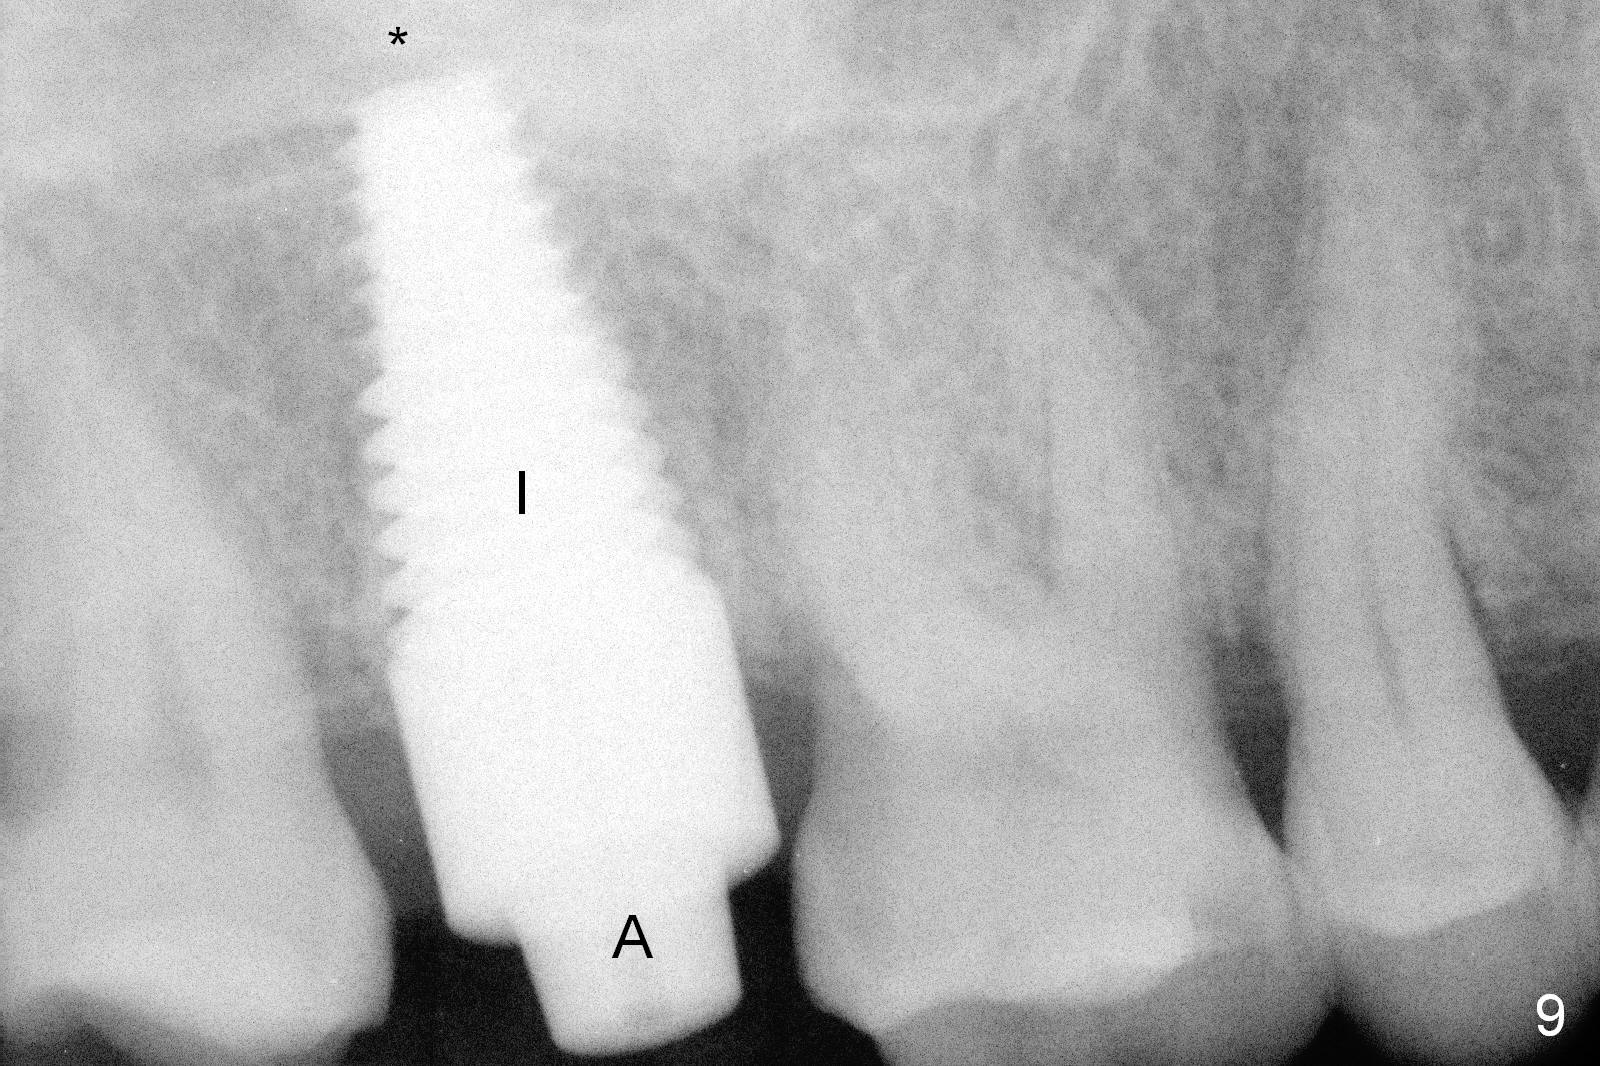

Osteotomy for immediate implant is initiated with a 2 mm pilot drill (Fig.6b red arrow) in the coronal end of the buccal slope of the septum (center of the socket). Once the drill gets initial penetration, the trajectory changes to the long axis of the tooth (Fig.6c). Then PA is taken with a parallel pin (Fig.7). It appears that the depth is not enough; there is bone apical to the pin. As osteotomy increases in diameter, burs may be deviated buccally due to the septal buccal slope (to be discussed below). With longer osteotomy, the deviation may be less. Osteotomy is deepened (Fig.6d). From this moment on, nose blowing test is done after each step. The result is all negative. As drill diameter increases, they do deviate buccally (Fig.6e arrow), since there is less bone contact buccally than lingually (compare Fig.6e,f). With the same reason, smaller tapered taps (Fig.6g pink, 5 and 6 mm) tend to be mobile buccally (arrow). When a large tap (7 mm) is inserted (Fig.8), there is no buccal mobility. It appears that the tap contacts more of the buccal plate (Fig.6h), but the coronal end of the tap is buccal (Fig.6i, pink circle). At each step of osteotomy, the coronal end of a bur or tap should be pushed as lingual as possible so that the final tap is favorable for restoration (Fig.6j). Sinus lift is done (Fig.6k red circle; Fig.9 *) before placement of 7x17 mm implant (I, >60 Ncm). Since the palatal socket is not associated with implant stability, it is closed by collagen plug (Fig.6l, blue area). As extra precaution, bone graft is placed around the coronal portion of the tissue-level implant (Fig.6l red circles), followed by collagen dressing.